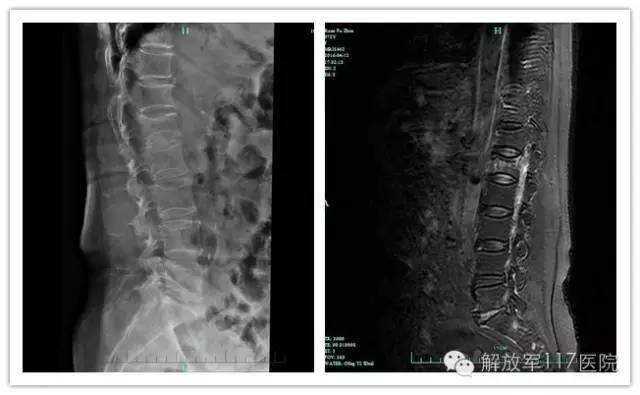

75岁的蒋雅仙是杭州本地人,近十余年来饱受腰背胀痛不适的困扰,活动劳累后疼痛加剧,同时出现腰部下坠感,休息后症状减轻。期间,她一直采用中医外敷膏药治疗,但始终不见好转。一个多月前腰背部在无明显诱因下疼痛加重,并向双侧大腿外侧扩散,随后前往117医院骨四科求诊。经X片检查,医生发现患者腰椎有退行性改变,给予卧床、药物止痛等治疗后症状稍有缓解,但并不显著。后查磁共振显示其椎体有压缩性骨折,随即以“骨质疏松伴病理性骨折”收治住院。结合患者病史资料和各项辅助检查,科室主任刘志荣为其行T9、T11经皮穿刺椎体成形术,仅用时不到一个小时便顺利完成手术,患者愈后良好,疼痛消失。

X片及MRI提示腰椎压缩性骨折

骨质疏松性椎体压缩性骨折是由于骨质疏松症导致的椎体在微小外力下发生的压缩性骨折,常见于老年人,多发于胸腰段椎体,可以导致骨折部位疼痛、椎体高度丢失、脊柱不稳,甚至导致脊柱后凸畸形。随着病情发展,其症状主要表现为骨折椎体部位的持续疼痛和脊柱活动受限,大大降低患者生活质量,更重者甚至导致死亡。